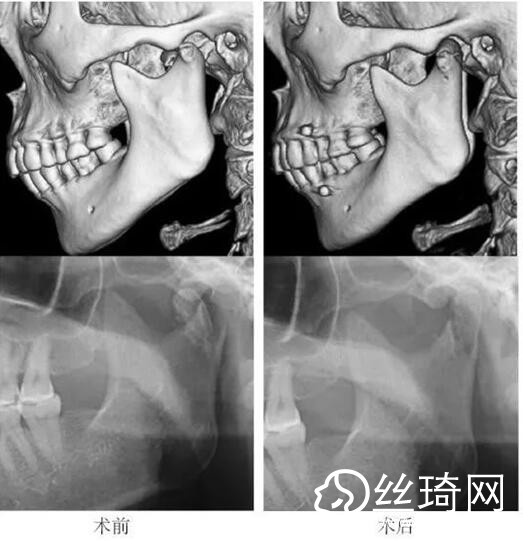

在106側(cè)中,髁突高位矢狀骨折46側(cè),中位髁頸骨折26側(cè),低位髁頸下骨折34側(cè)。髁突高位矢狀骨折及中位髁頸骨折均經(jīng)耳屏前徑路復(fù)位;34側(cè)低位髁頸下骨折中,經(jīng)耳屏前徑路復(fù)位13側(cè),頜下徑路復(fù)位19側(cè),頜后徑路復(fù)位1側(cè),穿腮腺?gòu)铰窂?fù)位1側(cè)。髁突高位矢狀骨折復(fù)位后以1~2枚可吸收長(zhǎng)螺釘固定(圖1)[3],采用的可吸收內(nèi)固定系統(tǒng)為BioSorb(ConMed Linvatec,芬蘭)、Inion OTPS(Inion,芬蘭);規(guī)格:直徑2 mm,長(zhǎng)度15~20 mm。中位髁頸骨折及低位髁頸下骨折多以2塊可吸收板固定(圖2)[3],個(gè)別病例以1塊或3塊可吸收板固定,采用的可吸收內(nèi)固定系統(tǒng)為BioSorb(ConMed Linvatec,芬蘭)、Grand Fix(Gunze,日本)、Inion OTPS(Inion,芬蘭);規(guī)格:直4孔板,孔徑 mm或2.5 mm,長(zhǎng)度21~35 mm,螺釘直徑 mm或2.5 mm,長(zhǎng)度7~10 mm??晌蔗敯宓氖中g(shù)操作采用專用器械工具盒,并遵照廠家操作指引進(jìn)行。

82例髁突骨折患者,術(shù)后隨訪6個(gè)月至3年,平均年。所有患者術(shù)后未訴明X不適,面型基本對(duì)稱,面部肌肉運(yùn)動(dòng)正常,咬合對(duì)位良好,開口度~4.2 cm,平均(±)cm。3例患者開口型輕度偏斜,均為髁突高位骨折,其中2例為粉碎性骨折行骨折碎片摘除,1例為矢狀骨折,以可吸收螺釘固定后,創(chuàng)口感染,隨后行局部清創(chuàng)并取出髁突骨折片及可吸收螺釘,創(chuàng)口愈合良好。96側(cè)髁突骨折中,2例髁頸下骨折術(shù)后復(fù)查CT顯示輕度移位,但患者無(wú)功能障礙,持續(xù)觀察,未做特殊處理。其他患者未見明X排斥反應(yīng)及并發(fā)癥。

本組病例中,絕大多數(shù)髁頸、髁頸下骨折均經(jīng)耳屏前或頜下切口進(jìn)行復(fù)位固定,均獲得了良好的復(fù)位固定性及療。有2例患者輕度移位,可能與過(guò)早承重及可吸收材料的強(qiáng)度較弱有關(guān)。